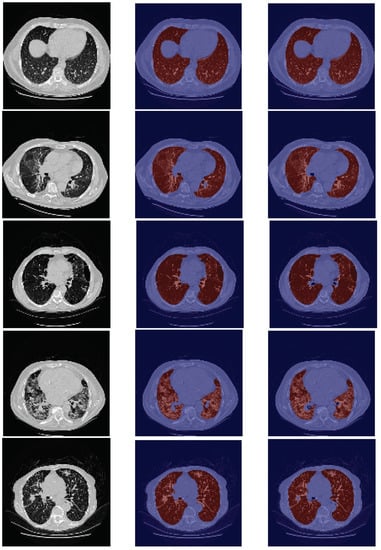

The results presented in Table 5 can be visually verified in Figure 3. For the specific cases of micronodules, bronchioectasis, emphysema, and some cases of fibrosis, the model is able to segment the entire lung area, as these are patterns which do not contain a higher contrast in tissues density (see respective examples on the first four rows of Figure 3). In general, those pathological cases showed a slightly better performance (Table 5).

Figure 3.

Examples of HUG-ILD images for pathological cases. The patterns of these images from top to bottom are, respectively, micronodules, bronchioectasis, emphysema, fibrosis, macronodules, reticulation with ground-glass, consolidation, ground-glass, and pneumocystis carinii pneumonia. For the last five examples, the model failed to segment part of the lung due to the pathological changes present in the image.

In contrast, for cases of macronodules, reticulation, consolidation, ground-glass, and pneumocystis carinii pneumonia, the model presents a difficulty in performing such tasks in the regions of higher density (see last five examples (rows) of Figure 3). Besides that, the scans from this dataset include the trachea and other respiratory structures (apart from the lungs) in their ground truth, elements that are not identified by the model, and thus contributing to a lower metric (see rows two–five in Figure 3). Once again the model fails to identify the slices corresponding to the base of the lung (see the second row in Figure 6).